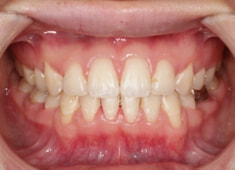

先天欠如歯両側上顎3番

治療法:フルパッシブブラケット:T21

治療後(2年9ヶ月後)